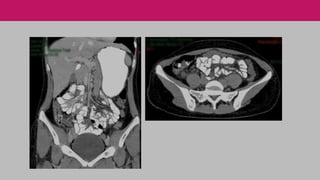

INVESTIGAÇÃO COMPLEMENTAR

Métodos de imagem

੦ tomografia computadorizada

• sensibilidade 87 a 100%

• especificidade 95 a 100%

• considerado o exame de maior confiabilidade

no diagnóstico de apendicite aguda

TOMOGRAFIA

Sensibilidade maior que o US.

Especificidade semelhante ao US.

Auxílio em outros diagnósticos.

Desvantagens:

੦ radiação;

੦ demora (quando usado contraste oral);

੦ efeitos colaterais do contraste intravenoso quando

utilizado: nefropatia ou reação alérgica.

Alto custo?

* Diminui internações e apendicectomias desnecessárias,

diagnóstico precoce em população específica (idosos).

#IMPORTANTE INVESTIGAÇÃO COMPLEMENTAR Métodos deimagem ੦ tomografia computadorizada • sensibilidade 87 a 100% • especificidade 95 a 100% • considerado o exame de maior confiabilidade no diagnóstico de apendicite aguda • critério de Alvarado 4 a 6

TOMOGRAFIA Sensibilidade maior queo US. Especificidade semelhante ao US. Auxílio em outros diagnósticos. Desvantagens: ੦ radiação; ੦ demora (quando usado contraste oral); ੦ efeitos colaterais do contraste intravenoso quando utilizado: nefropatia ou reação alérgica. Alto custo? * Diminui internações e apendicectomias desnecessárias, diagnóstico precoce em população específica (idosos).